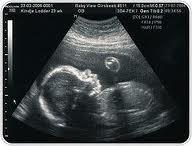

Estaba embarazada, después de tanto tiempo buscándolo y de la ayuda de los médicos, estábamos embarazados y no podíamos ser más felices. Las embarazadas no son enfermas, lo pensaba y lo sentía, pero yo iba al médico con miedo de que algo estuviera mal; tanta analítica, tanta consulta, tan poco diálogo… entraba por la consulta sintiendo por favor dime que he aprobado. Nunca sentí que realmente importáramos ni mi hija ni yo, sólo eran positivos o negativos en una hoja. Creo que dentro de mí sabía que las cosas no eran como no las vendían…la prueba del azúcar… ¿le dan a un posible hipertenso una sobrecarga de sal a ver si le da un “jamacuco”? – No-. Pero ahí estaba yo en el hospital, porque la prueba corta me había dado justo en el borde. Mareada, tuvieron que tumbarme para soportar el mal cuerpo y confirmar lo que la ausencia de síntomas ya había dicho: mis niveles de glucemia eran normales. Recuperé ese recorte de revista en el que hablaban de un libro: “La revolución del nacimiento”, de Isabel Fernández del Castillo. Lo había guardado mucho tiempo atrás porque mencionaban que la postura en la que se pare en la mayoría de los hospitales españoles no es la óptima, algo que siempre había pensado. Por esta razón dudé de si comprarme o no el libro, pensaba que al leerlo solo conseguiría sentir que mi bebé y yo nos íbamos a perder algo; que aquí las cosas no podían ser de otra manera… pero al final pudo más mi sed de lectura, de aprender. En ese momento no sabía lo que ese libro iba a suponer en mi vida. Me planteé con el libro crear un plan de parto, pero la matrona del curso de preparación al parto me dijo que no iba a servir de nada. Mi entorno me decía que no fuera “listilla”, que los médicos son los que saben. Entonces una socia me llamó y me tendió esa mano que necesitaba para por lo menos intentarlo. Me citaron a consulta. Lo que más me preocupaba (además de la episiotomía) era saber si me darían a mi hija nada más nacer. Recuerdo perfectamente a la ginecóloga diciéndome que eso daba igual que tenía toda la vida para estar con la niña. No hubo conversación ni intercambio de opiniones. Sólo me dijeron que confiara en ellos que lo iban a hacer lo mejor posible. Viví mi embarazo con miedo, con temores, respirando cada vez que me decían está todo bien. Y luego mi plan de parto no fue respetado, nuestro parto no fue nuestro, fue de ellos. Gracias a una lactancia prolongada y a esta Asociación me he perdonado por no hacer algo más. He aprendido y sigo aprendiendo que el embarazo es nuestro y espero algún día vivir la experiencia como lo que es: algo fisiológico, normal. Algo en lo que nosotras y nuestros bebés somos lo que más vale. Lo único que importa.